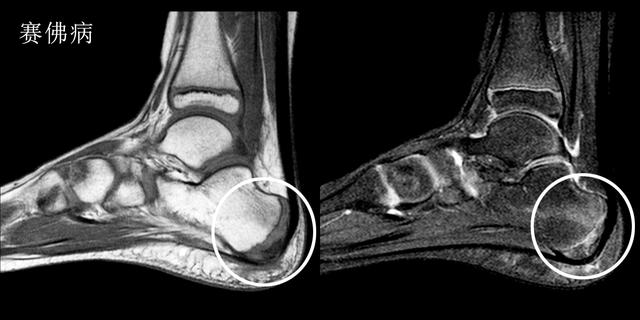

赛佛病---孩子也会得的跟痛症

足部是第一个成长为全尺寸的身体部位之一。这通常发生在青春期早期。在此期间骨骼通常比肌肉和肌腱生长得更快结果肌肉和肌腱变得紧绷,使鞋跟区域变得不那么柔软。在承重活动期间,会伤到脚跟诱发疼痛导致塞弗病(Sever's Disease)

赛佛病主要的症状是在运动时,尤其是跑跳时出现明显的足跟痛

在生长突增期间,您的孩子在青春期早期受伤的风险最大。

Sever病在8至10岁的身体活跃女孩中最常见。最常见的是10岁至12岁的身体活跃男孩。足球运动员和体操运动员经常得到塞弗病。任何跑步或跳跃活动的儿童也可能面临更大的风险。Sever's疾病很少发生在年龄较大的青少年身上,因为足跟的背部通常在15岁时完成。

这种疾病诊断主要还是依靠核磁检查,在核磁图像中我们可以看到明显的跟骨周边的无菌性严重表现,从而判断孩子是否得了赛佛病。

这种疾病的治疗以保守治疗为主,冰敷、休息以及外用药物可以得到很好地治疗效果

疾病治疗的难点不在于治,而在于是否能否发现孩子患病!